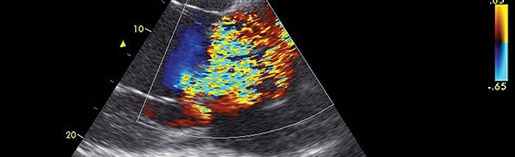

Gunther van Loon graduated from Ghent University, Belgium, in 1992 and has worked at the Ghent University, Department of Large Animal Internal Medicine, ever since. In 2001 he finished his PhD on “Atrial pacing and experimental atrial fibrillation in equines”. In 2004 he became Diplomate of the European College of Equine Internal Medicine and in 2011 Associate Diplomate of the European College of Veterinary Diagnostic Imaging. In 2015 he received the Merial Applied Equine Research Award for outstanding research regarding ‘Advances in Equine Cardiology’, awarded by the WEVA. He is Full Professor in Large Animal Internal Medicine at Ghent University and his major interests are all aspects of cardiology, and thoracic and abdominal ultrasound. Areas of research include advanced imaging (speckle tracking, tissue Doppler, 3D, intracardiac echo), biomarkers, vascular disease, and arrhythmias and electrophysiology (atrial tachycardia/fibrillation, 3D mapping, ablation). Gunther has published mainly in the field of equine internal medicine and cardiology and lectures regularly at national and international courses and conferences.